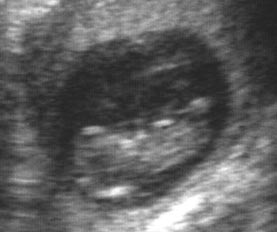

March 15, 2003 (10 weeks, 3 days)

March 21, 2003 (11 weeks, 2 days)

Our first ultrasound - probably the most incredible experience of my life so far. (click above to see the full image) The head is on the lower left, and the baby is resting on his or her back, kind of angled upward. With a little imagination, you can see one eye. In the ultrasound itself, we could see the little arms waving and legs kicking.